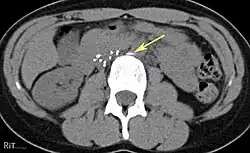

Of these IVC filter side effects, 328 involved device migration, 146 involved embolizations after detachment of device components, 70 involved perforation of the IVC, and 56 involved filter fracture. Much of the medical community believes that this large number of adverse events is related to the heart filter remaining in place for longer than necessary.

- Perforation of the vena cava

- 9% (12 of 132 patients) delayed filter penetration of the IVC greater than 3 mm

Review of prior cross-sectional imaging or a venogram of the IVC is performed before deploying the filter to assess for potential anatomic variations, thrombi within the IVC, or areas of stenoses, as well as to estimate the diameter of the IVC. Rarely, ultrasound-guided placement is preferred in the setting of contrast allergy, chronic kidney disease, and when patient immobility is desired. The size of the IVC may affect which filter is deployed, as some (such as the Birds Nest) are approved to accommodate larger cavae. There are situations where the filter is placed above the renal veins (e.g. pregnant patients or women of childbearing age, renal or gonadal vein thromboses, etc.). Also, if there is duplication of the IVC, the filter is placed above the confluence of the two IVCs [45] or a filter can be placed within each IVC.[46]